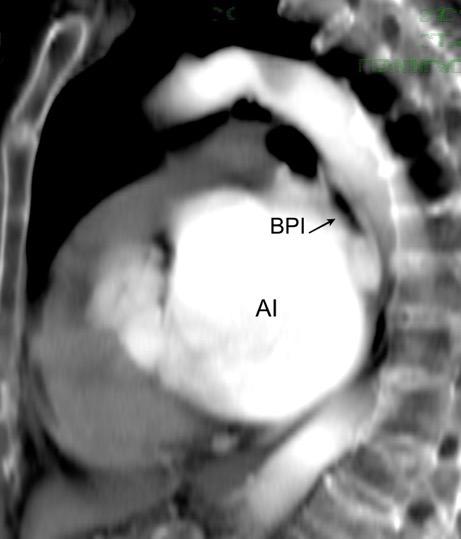

53. BPI .COMPRESIÓN Y DESPLAZAMIENTO HACIA ARRIBA DEL

La presencia de tumor o ganglios rodeando el BPI hace que este aparezca como mucho más nítido y definido.